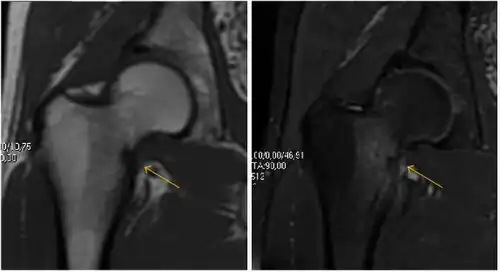

Figure 9:

Sagittal T1 weighted image showing anterosuperior labral tear.[1] -

Sagittal T1 weighted image showing chondral lesion.[1] -

Sagittal CT-arthrography showing posteroinferior chondral injury.[1] -

Coronal CT-arthrography (d) showing ligamentum teres tear.[1]

MR arthrography has proven superior in accuracy when compared to native MR imaging. It is considered the best technique to assess the labrum. Knowledge of the normal variable morphology of the labrum helps to differentiate tears from normal variants. A triangular shape is most commonly seen in 66% of asymptomatic volunteers, but round, flattened, and absent labra can also be found in asymptomatic populations. MR arthrography has demonstrated sensitivity over 90% and specificity close to 100% in detecting labral tears. Loose bodies are demonstrated as filling defects surrounded by the hyperintense gadolinium.[1]

Association between labral tears and chondral damage has been demonstrated. This underscores the interaction between cartilage and labrum damage in the progression of osteoarthritis. Chondral damage to the posteroinferior part of the acetabulum as a contrecoup lesion occurs in approximately one-third of pincer cases secondary to persistent abutment on the anterior part of the joint leading to a slight posteroinferior subluxation. This is considered a bad prognosis sign.[1]

MR arthrography can also demonstrate ligamentum teres rupture or capsular laxity, which are debated causes of microinstability of the hip. Elongation of the capsule or injury to the iliofemoral ligament or labrum may be secondary to microtrauma in athletes. MR can demonstrate abnormalities in these cases, such as increased joint volume or a ligamentum teres tear (Figure 9).[1]

Most of the angles and measurements described in the plain radiograph section can be accurately reproduced on MRI. In addition, the superiority of MRI resolution with intra-articular contrast allows detection of labral and chondral abnormalities that may influence the choice of medical, percutaneous, or surgical management (Figure 9).[1]